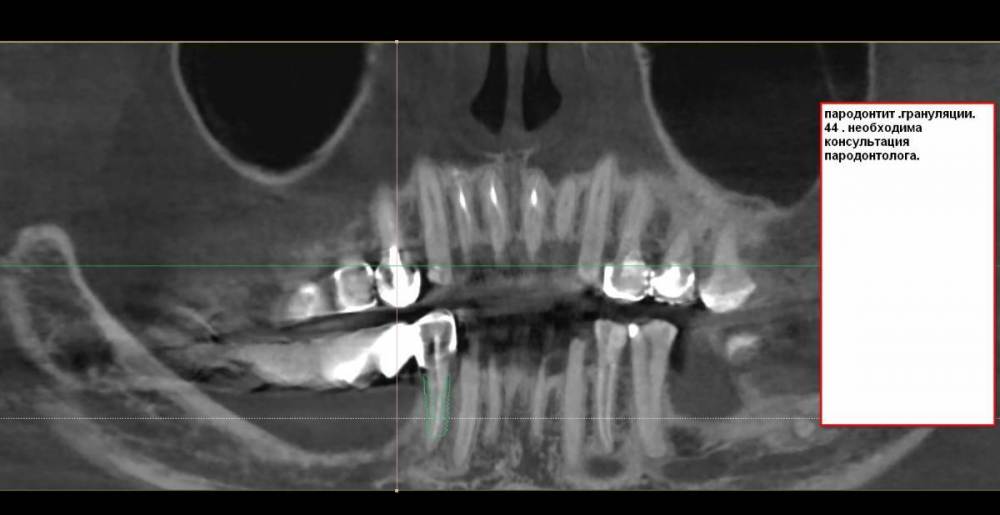

Вот с такой ситуацией обратилась к врачу, болел зуб мудрости.  Далее был сделан снимок (прилагаю фото решений- удаление опорных зубов с последующей заменой имплантами). PX20171201_162103_0000_000000FF.thumb.jpg.8c974cf49da3bb77db059abb91c7264c.jpg2018-01-24_013834.thumb.jpg.48a661d2a2f2d78a18d7b2906252d0a3.jpg2018-01-24_014845.thumb.jpg.0665ffa758959ace3ce9d7a8ff27421f.jpgпосле проведенных манипуляции появилась парастезия тройничного нерва, считаю это последствиями неверно установленного импланта, справедливо ли мое мнение?  Прохожу длительное лечение у невропатолога.  На крайнем визите врач отказал в помощи с этой проблемой и с обнаженным имплантом. (Прикладываю фото) 786267296_09_12_21.thumb.jpg.f332c30c240cb1ba19d2341b4f6014f1.jpg20220116_233530.thumb.jpg.c9cc82f18d25e9a905a2b7b1dc13eb8c.jpg20220116_232905.thumb.jpg.c3953c0b472c6e3ce1f46272ef507d2e.jpg1915694342_WhatsAppImage2022-08-20at19_39_20.thumb.jpeg.2099829af18d4d8c448126d5f323605f.jpegУ меня следующий вопрос:  верно ли назначенное лечение и насколько корректно установлены импланты, а также имелись ли противопоказания для установки имплантов, имея ввиду, что была убыль кости? Можно ли устанавливать импланты в таком случае?  прикладываю фото уже удаленного установленного на на импланты моста, правильно ли выполнен технически? (импланты пришлось удалить, а мост снять, чтобы сделать операцию по восстановлению кости, но уже в другой клинике. так как, как я писала выше, врач, установивший импланты отказал в помощи).

План лечения в виде удаления зубов и установки имплантов был назначен вам верно. Вариант с увеличением костной ткани и последующей имплантацией предпочтительней,чем ставить импланты без костной пластики. Но вариант,который делал первый доктор тоже не запрещен,видимо что то пошло не так